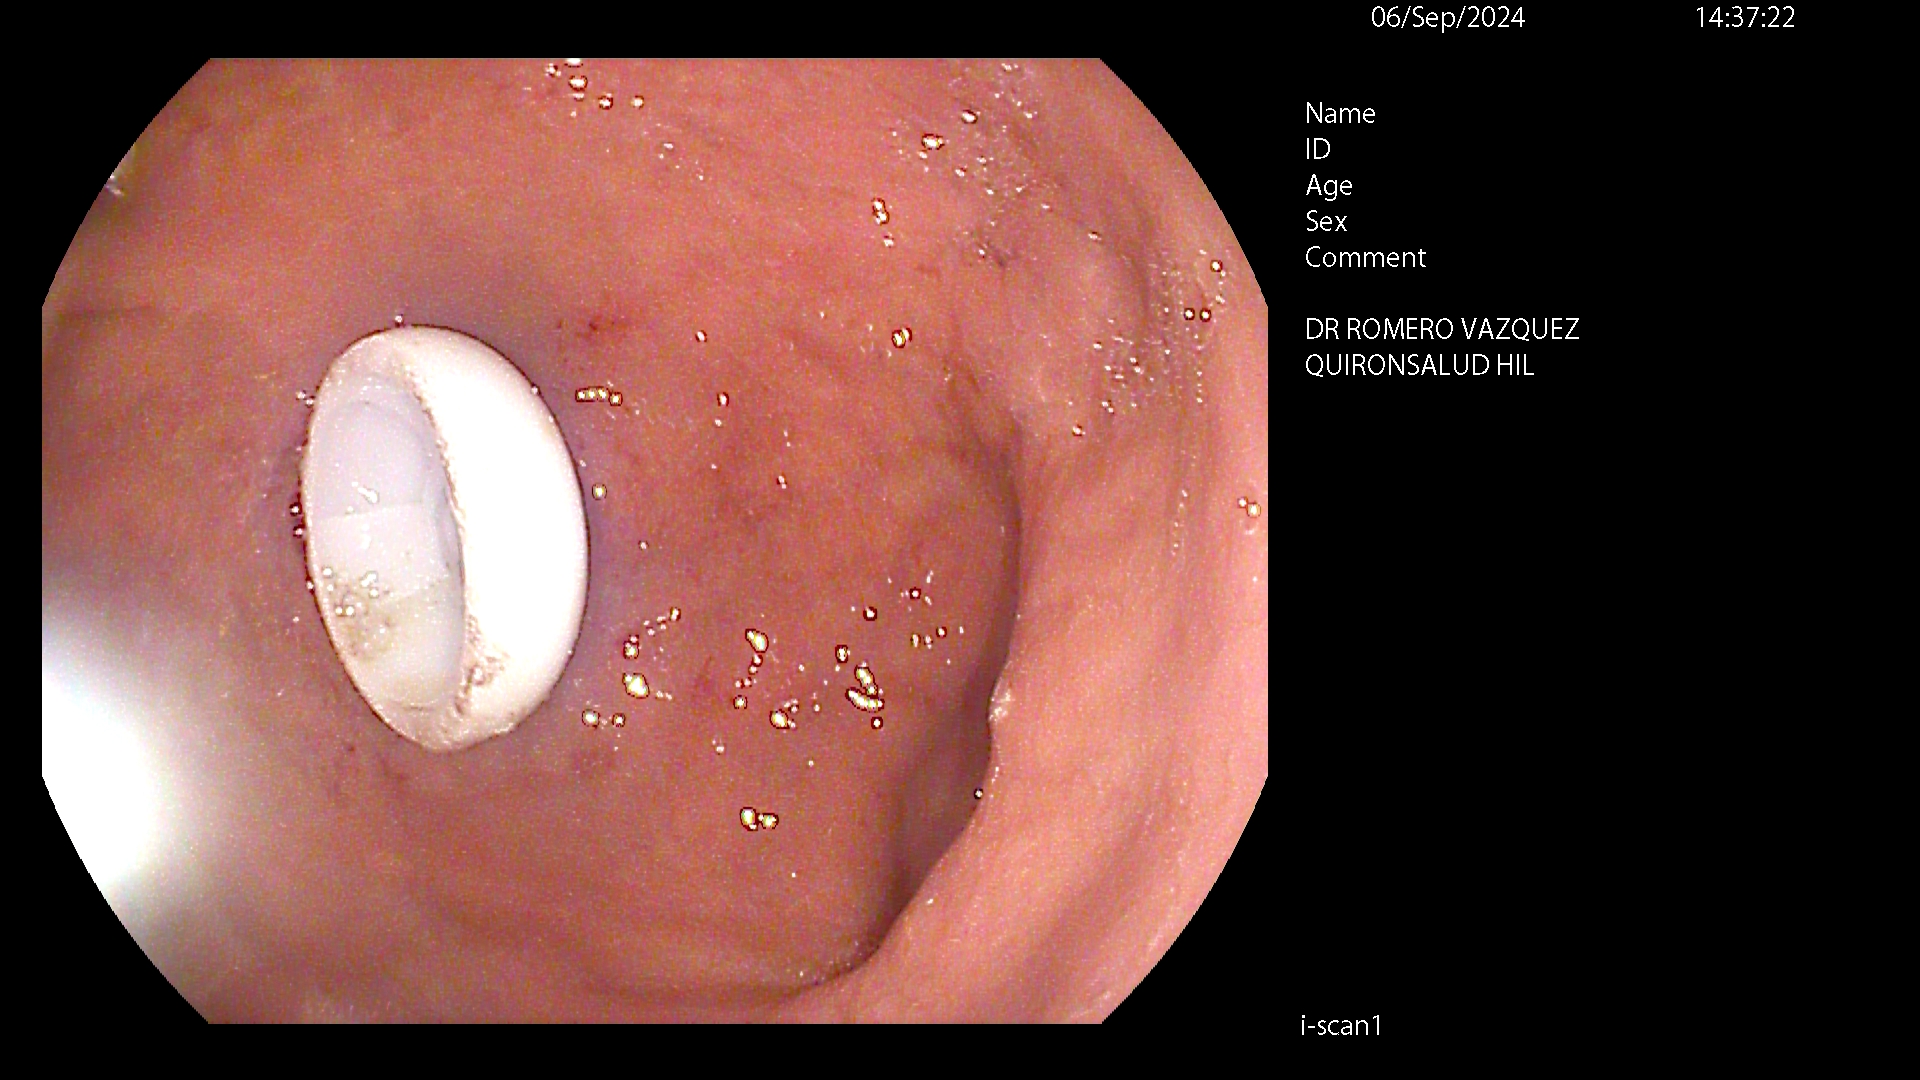

Es una sonda de larga duración precisando sólo recambios, fáciles de realizar en unos 4-6 meses, dependiendo del deterioro propio de la sonda. Normalmente, el primer recambio precisa asistencia endoscópica con sedación profunda y los siguientes no requieren endoscopia ni sedación por anestesista, realizándose de forma ambulatoria.

La sonda queda sujeta por un botón gástrico o balón en el estómago y un disco ajustable sobre la piel.